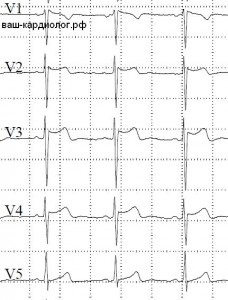

Képek channelopathiák EKG (elektromos szívbetegségek primer)

Brugada szindróma - egy örökletes elsődleges elektromos szívbetegség (channelopathiák) tele hirtelen halál a beteg. EKG eltéréssel tipikus kép a mellkas jobb vezet - kombinációja blokád His-kötegen, jobb láb ( „fül” a V1-V2) és a korai repolarizáció (kifejezett magasság ST) a V2-V3.

↓ Brugada szindróma nyereg-back (nyereg-alakú) formában. Jellemző változás a jobb mellkasi vezet.

↓ Brugada szindróma. Egy egység (jobb) „teljes» coved-komplexum.